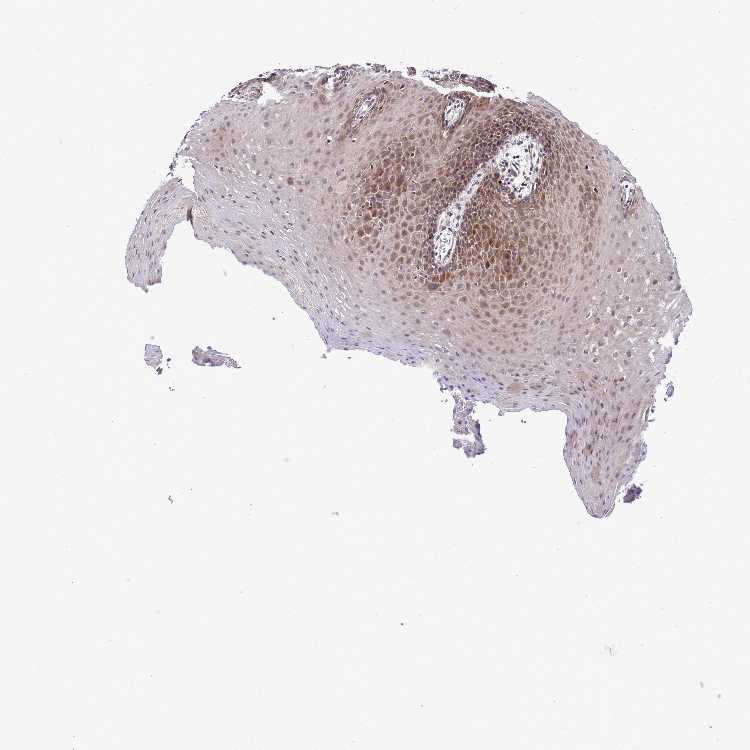

TISSUE PRIMARY DATA ORAL MUCOSA Show tissue menu

ORAL MUCOSA - Antibody stainingi

Antibody staining in the annotated cell types in the current human tissue is reported as not detected, low, medium, or high, based on conventional immunohistochemistry profiling in selected tissues. This score is based on the combination of the staining intensity and fraction of stained cells.

Each image is clickable and will lead to virtual microscopy that enables deeper exploration of all samples and also displays staining intensity scores, fraction scores and subcellular localization as well as patient and tissue information for each sample.

Antibody HPA047896

Squamous epithelial cells Medium